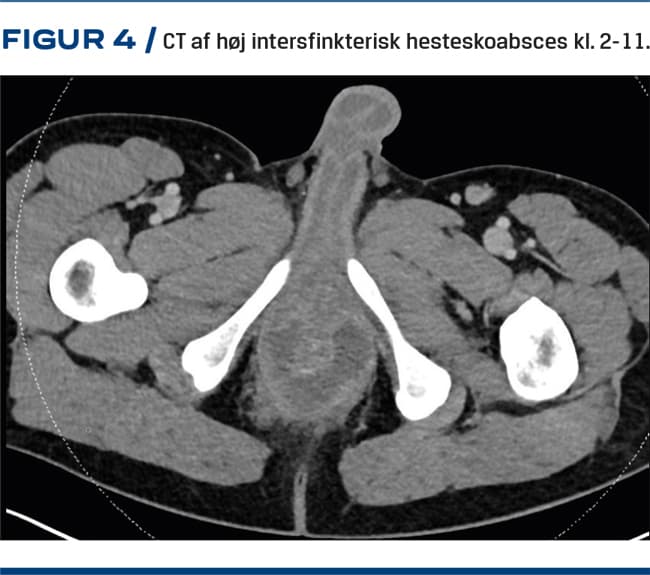

Hesteskoabsces

Når infektionen spreder sig fra en krypt i midtlinjen og lateralt til begge sider, anvendes betegnelsen hesteskoabsces (Figur 4). Hesteskoabsces forekommer næsten altid posteriort, da analkanalen fortil er stramt bundet til centrum tendineum og de foranliggende strukturer. En hesteskoabsces kan ses iskioanalt, intersfinkterisk og supralevatort [5, 11].

CT med intravenøs kontrast kan typisk udføres døgnet rundt. Hvis der er mistanke om en supralevator absces, høj intersfinkterisk absces eller hesteskoabsces som baggrund for sepsis, kan en CT give afklaring i vagten [21] (Figur 4).